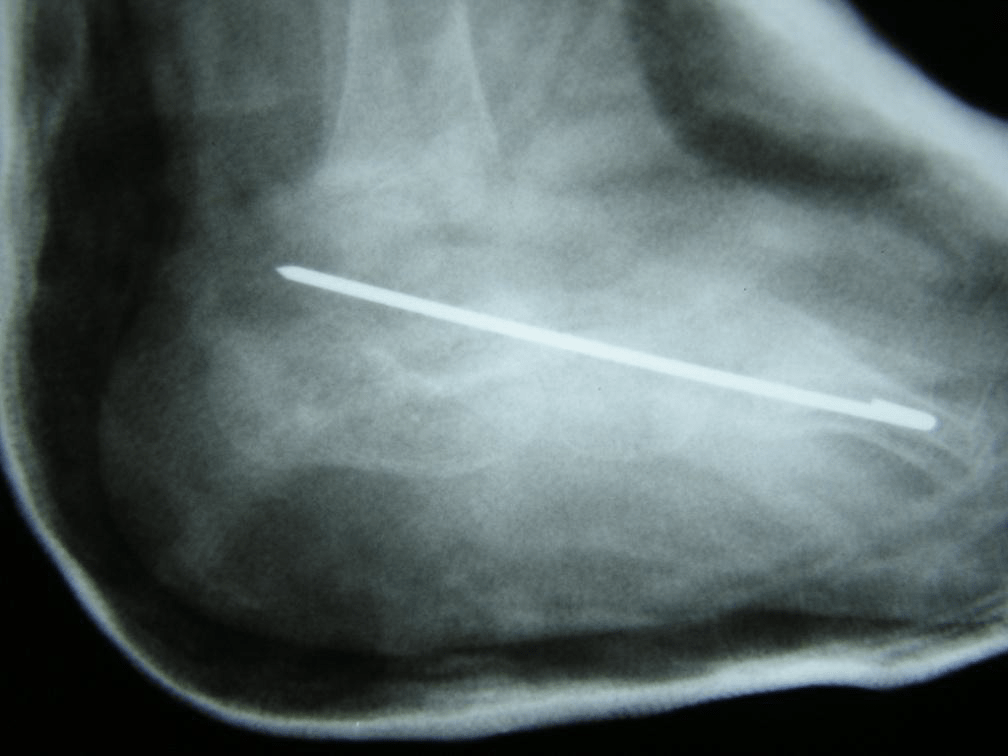

Figure 4: Post-op lateral views of both feet. The talo-navicular joints have been reduced and fixed.